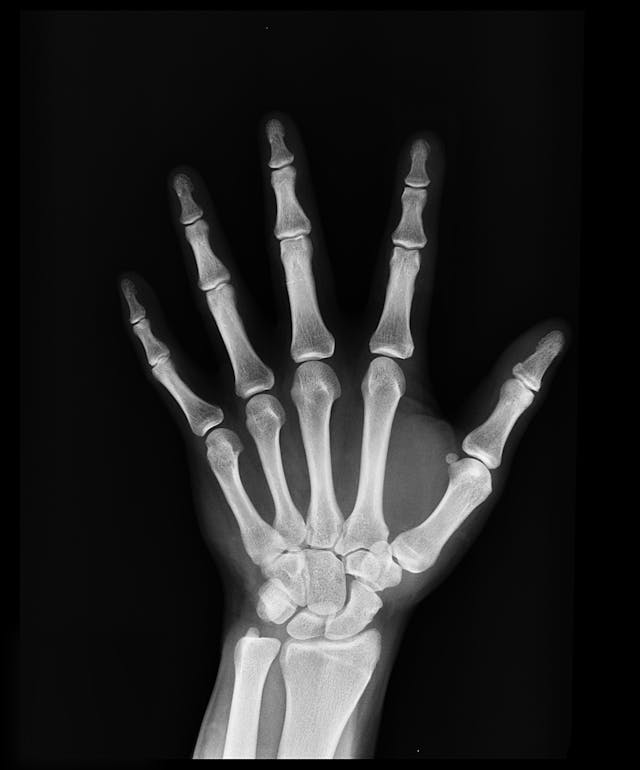

- 성장판 검사 방법 엑스레이를 통한 골연령 검사로 성장판의 상태와 남은 성장 가능성을 평가할 수 있습니다. 왼손 손목 X-ray가 가장 일반적으로 사용됩니다.

골연령(Bone Age) : 아이의 뼈 성숙도를 나타내는 지표로, 실제 나이와 다를 수 있습니다. 성장 잠재력을 예측하는 데 중요한 정보를 제공합니다.